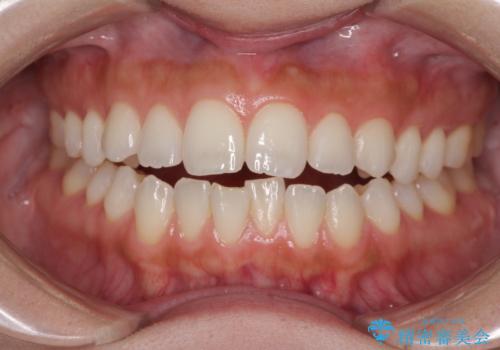

上下前歯のデコボコをきれいに インビザラインによる矯正治療

ワイヤー矯正を併用したことで前歯の叢生を速やかに解消することができました。

一方口元の突出感を改善するために時間がかかり、2年超を要しましたが、満足のいく仕上がりとなりました。